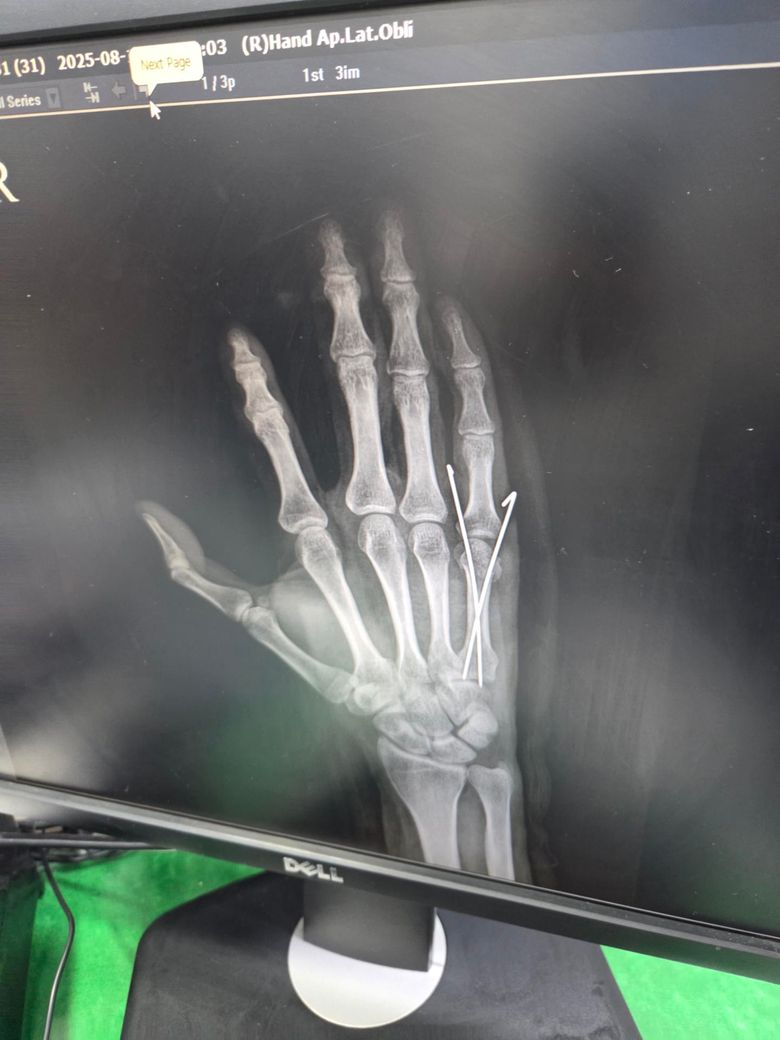

중수골 골절 수술 잘된건지 봐주세요?

의사 선생님이 너무 성의 없는 말투로 수술이 잘 됐다고 하셔서 불안해 남깁니다.

수술 직후 사진이고요

두 번째 사진을 보시면 수술한 손가락이 다른 손가락에 비해 뼈가 잘 정렬이 안 된 것 같아서요. 수술적으로 잘못된 부분이 있는지 알려주시면 감사하겠습니다.

• 1번 째 사진

엑스레이상으로는 금속 핀을 박은 수술로 보이며 사진상 정확한 상태 확인이 어렵긴 하지만 크게 정렬이 틀어지거나 문제는 없는 것으로 보입니다.

제가 직접적으로 수술의 판단해 드리긴 어렵습니다. 다만 사진상으로는 금속 핀 고정으로 뼈 정렬을 잡은 흔적이 보이며 수술 직후에는 약간의 틀어짐이 있어도 시간이 지나면서 유합과정에서 교정되는 경우가 많습니다.